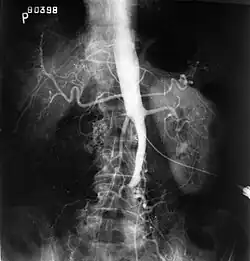

Sensibilisé par les nombreux blessés de la Première Guerre mondiale, il est l'un des premiers à mettre en pratique une chirurgie douce, économe en sang et aussi peu traumatisante que possible. Il est spécialiste de la douleur, de la chirurgie vasculaire et du tronc sympathique. Deux syndromes portent son nom, l'algoneurodystrophie et l'oblitération aorto-iliaque.

Chirurgie vasculaire et du sympathique

L'entre-deux guerre voit l'apparition de l'artériographie qui permet de mieux comprendre des maladies telles que l'artériopathie des membres inférieurs. Leriche est d'avis que l'athérosclérose revient à un problème local d'obstruction susceptible d'une correction chirurgicale. Il considère que le segment artériel obstrué se comporte comme un nef vasoconstricteur, ce qui peut être corrigé par sympathectomie, en l'occurrence la sympathectomie lombaire[8].

- (en) avec André Morel, The Syndrome of Thrombotic Obliteration of the Aortic Bifurcation, Annals of Surgery, (lire en ligne).

- Syndrome de Leriche : oblitération thrombotique de la bifurcation aortique[47].